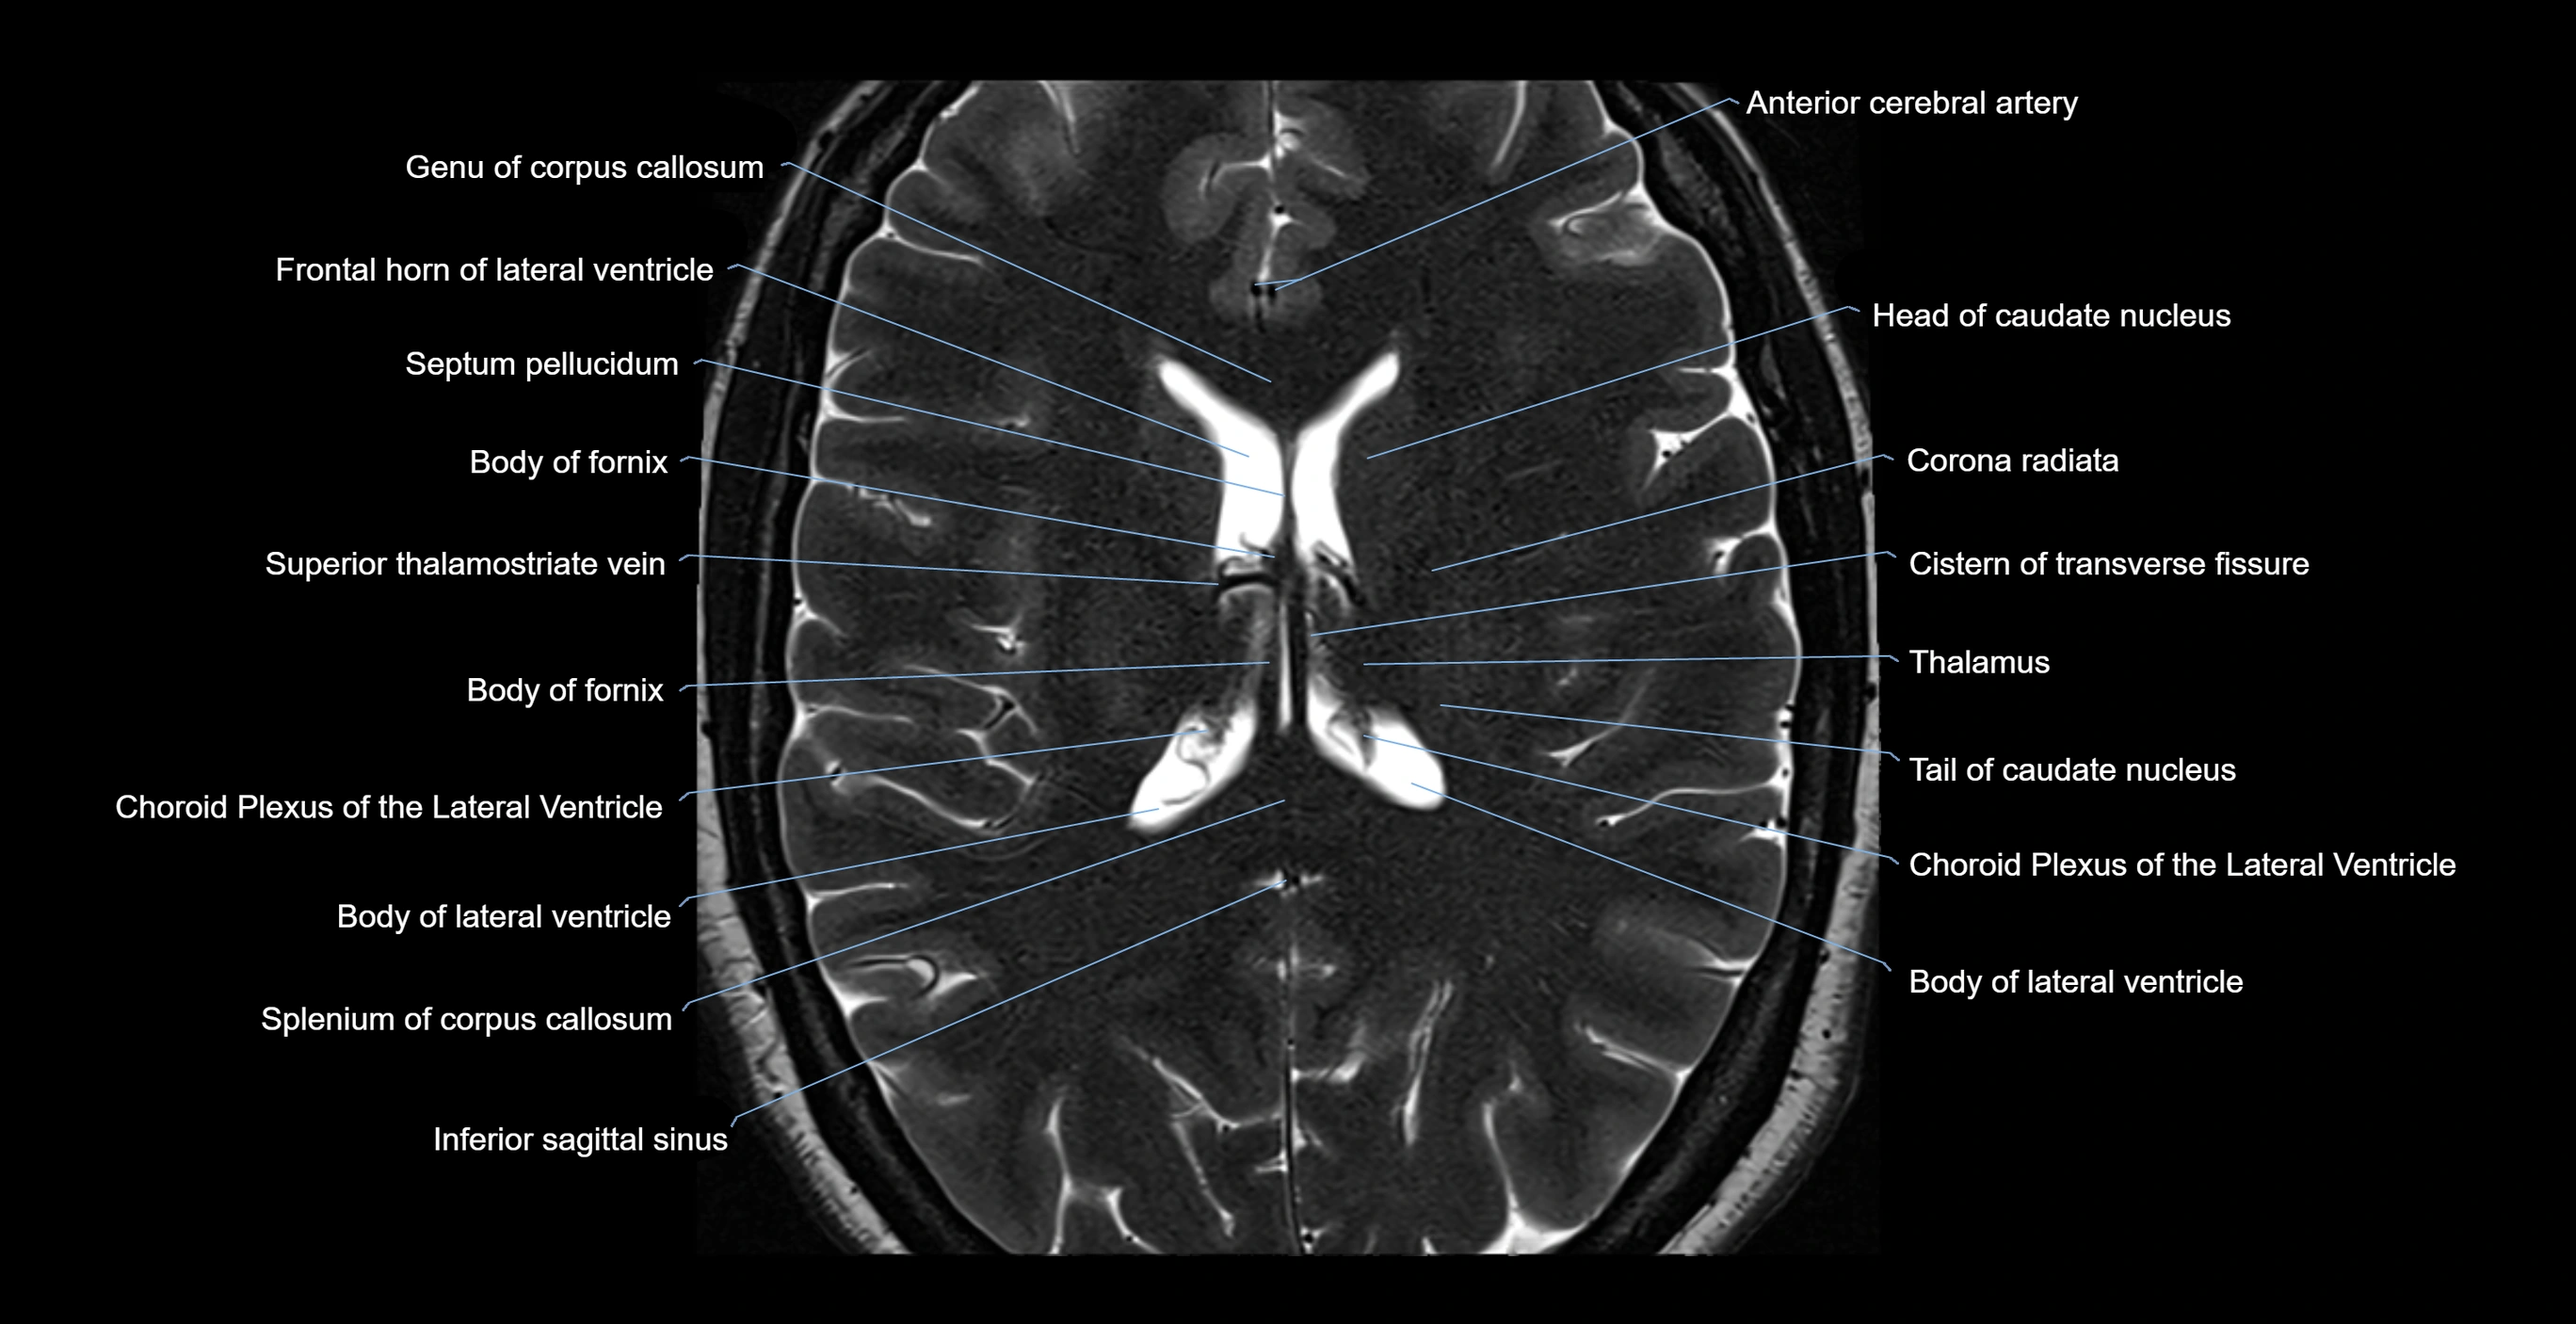

MRI images